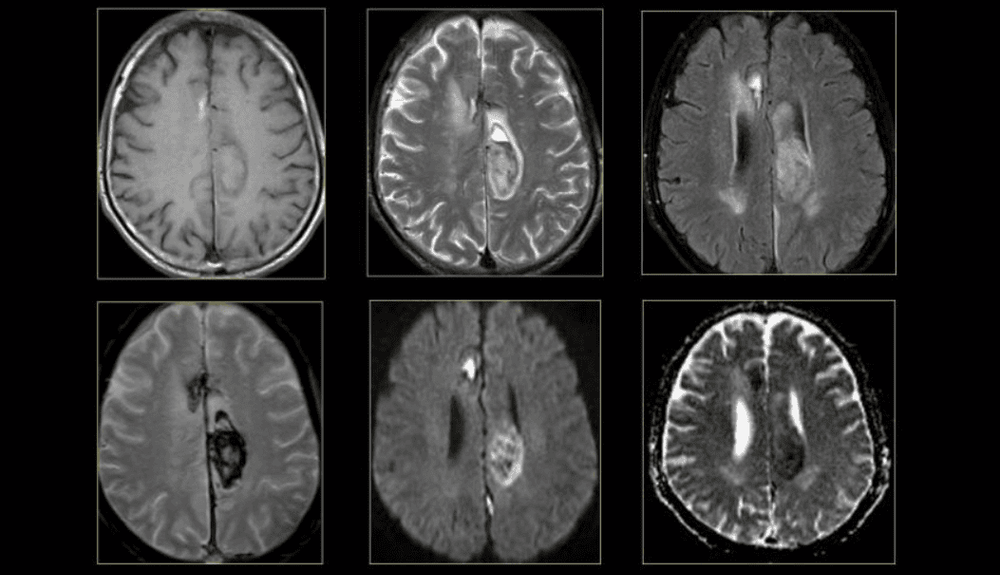

3.1 MRI của não và tủy sống

MRI là phương pháp xét nghiệm hình ảnh được sử dụng thường xuyên nhất đối với não và tủy sống. MRI thường được thực hiện để giúp chẩn đoán:

Một loại MRI đặc biệt - MRI chức năng của não (fMRI), có thể tạo ra hình ảnh của lưu lượng máu đến các khu vực nhất định của não. Nó có thể được sử dụng để kiểm tra giải phẫu não và xác định phần nào của não đang xử lý các chức năng quan trọng.

Điều này giúp xác định các khu vực kiểm soát chuyển động và ngôn ngữ quan trọng trong não của những người được xem xét phẫu thuật não. MRI chức năng cũng có thể được sử dụng để đánh giá thiệt hại do chấn thương đầu hoặc do các rối loạn như bệnh Alzheimer.

Hình ảnh não bộ trên MRI